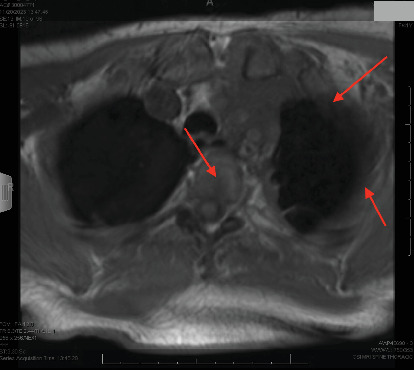

Epithelioid hemangioendothelioma (EHE) is an extremely rare vascular sarcoma that can initially present with a myriad of symptoms anywhere in the body. Imaging findings are often nonspecific, and the pathology tends to have overlap with other malignancies. As a result, it can be quite difficult to suspect and diagnose EHE. We present a case of pulmonary EHE in a 41-year-old female with left pleural thickening and subclavian tumor thrombus who was initially misdiagnosed and treated as mesothelioma. This instance demonstrates the importance of maintaining a broad differential and the utilization of repeat biopsies and next-generation sequencing for questionable diagnoses of atypical malignancies.

Abstract Image